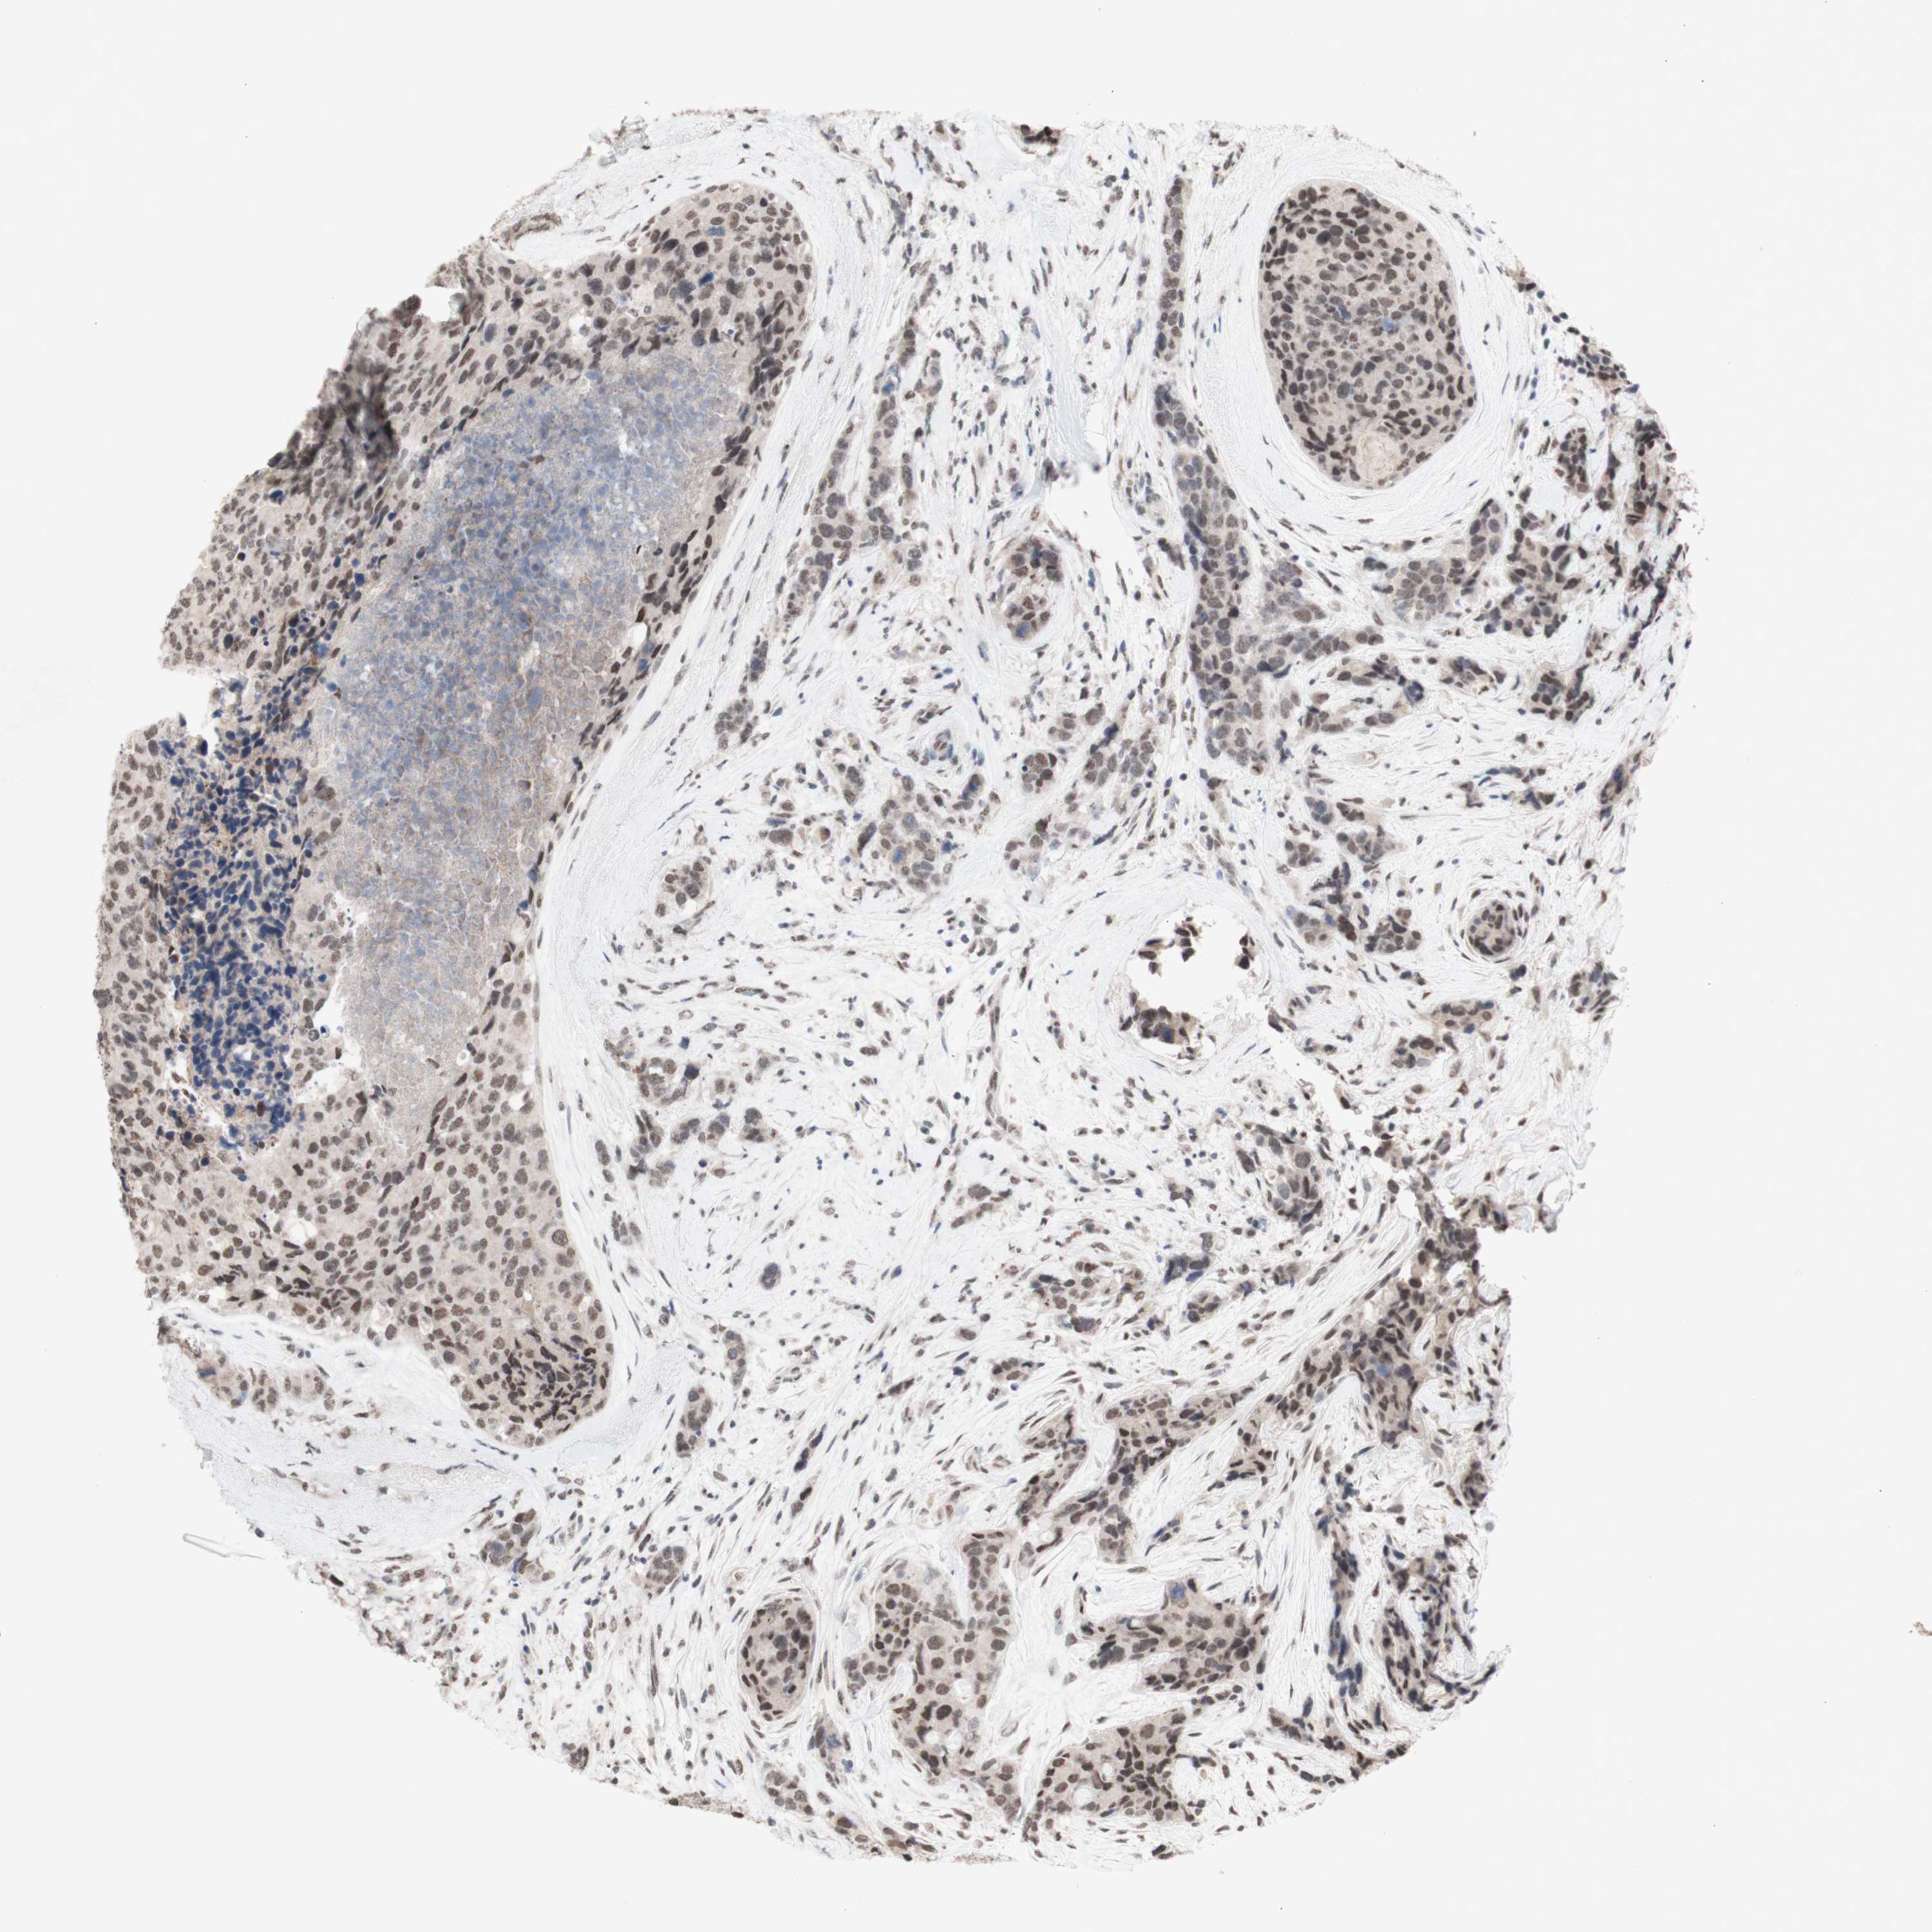

CANCER BREAST CANCER Show tissue menu

BRCA TCGA BRCA VALIDATION PROTEIN EXPRESSION

ANTIBODIES

AND

VALIDATION